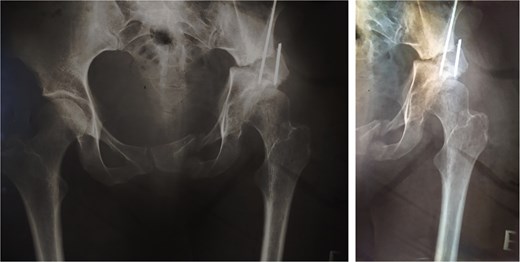

Thirteen years after THA, the 76-year-old patient continued to have a stable asymptomatic hip. Hip radiographs showed unchanged and stable positioning of the acetabular cup and femoral stem, with no measurable subsidence or radiolucent lines around the components (Fig. 4).

Postoperative anteroposterior radiographs of the pelvis 13 years after the THA, showing mechanical stability of the prosthesis with no evidence of loosening. No signs of osteoarthritis are present in the right hip (Tönnis Grade 0).